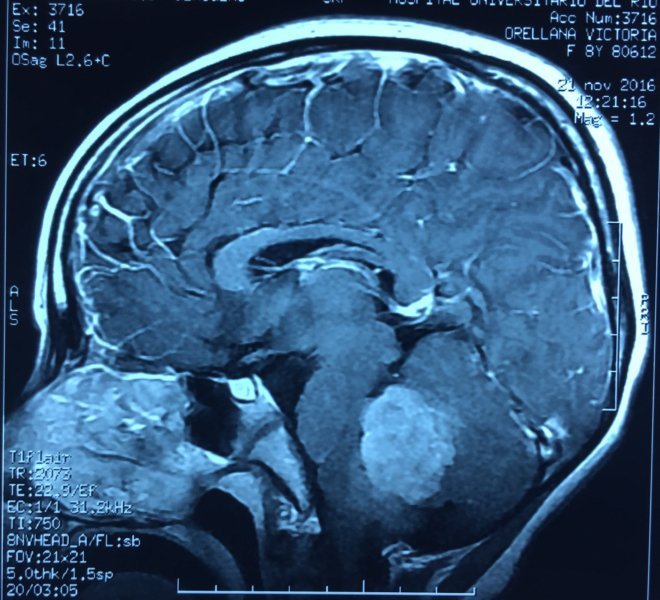

MEDULOBLASTOMA

DESCRIPCIÓN